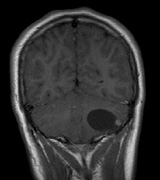

CNS hemangiomas are the most common tumor of VHL, affecting 60% to 80%, with a predilection for the cerebellum and spinal chord. An enlarging cystic component is a frequent finding in symptomatic tumors. Patients typically present in their early 30s; headaches or neck pain in affected individuals should not be ignored.172,173 On microscopy, CNS hemangiomas resemble retinal capillary hemangiomas. Their malignant potential is low.174 The treatment is surgical (Fig. 17, A and B).13

Fig. 17. Images from a 13-year-old boy with Von Hippel-Lindau syndrome. (a) Coronal postcontrast T1-weighted imaging reveals a cystic lesion with an enhancing nodule at the pial surface typical of a hemangioblastoma. (b) A second solid enhancing hemangioblastoma is seen at the craniocervial junction on a sagittal postcontrast T1-weighted image. (c) Associated cystic lesions (arrows) are seen within the pancreas.